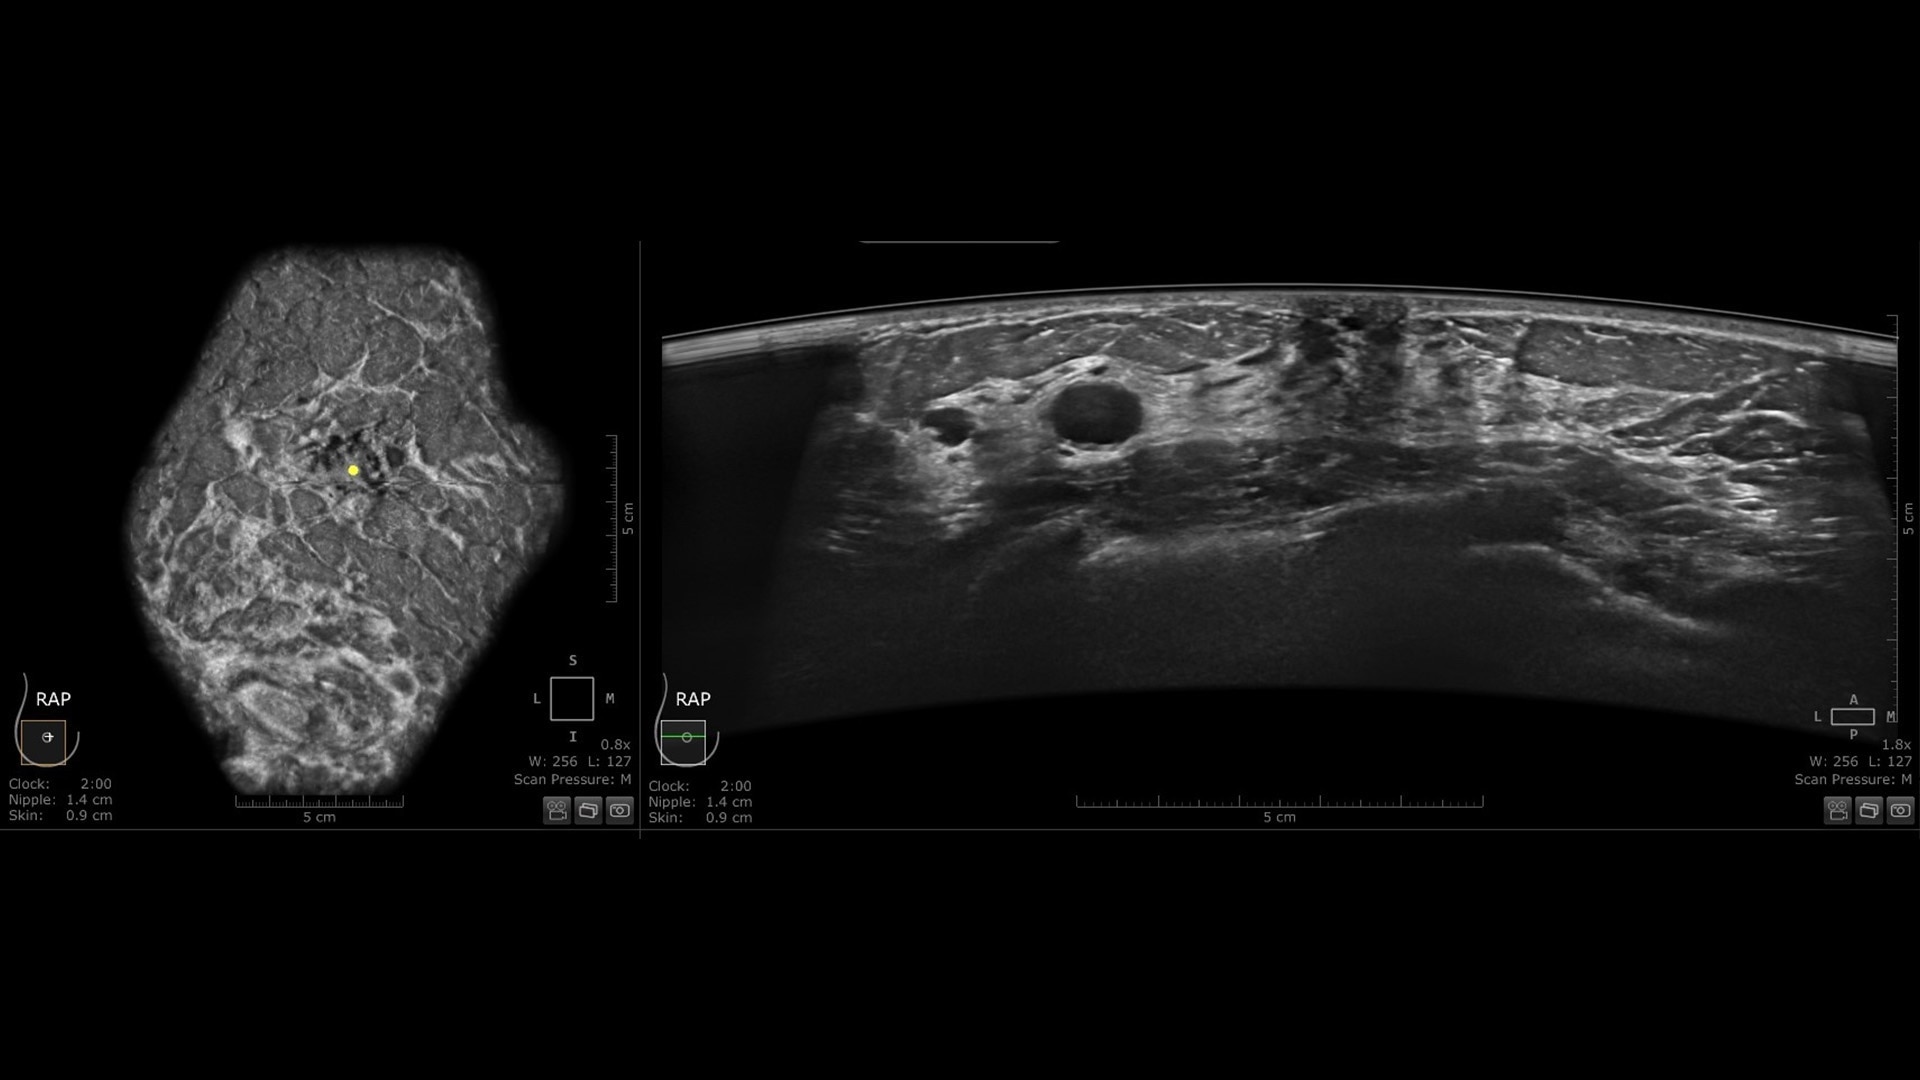

Productivity powered by AI

Boost clinical confidence and efficiency with AI-driven scanning and reading